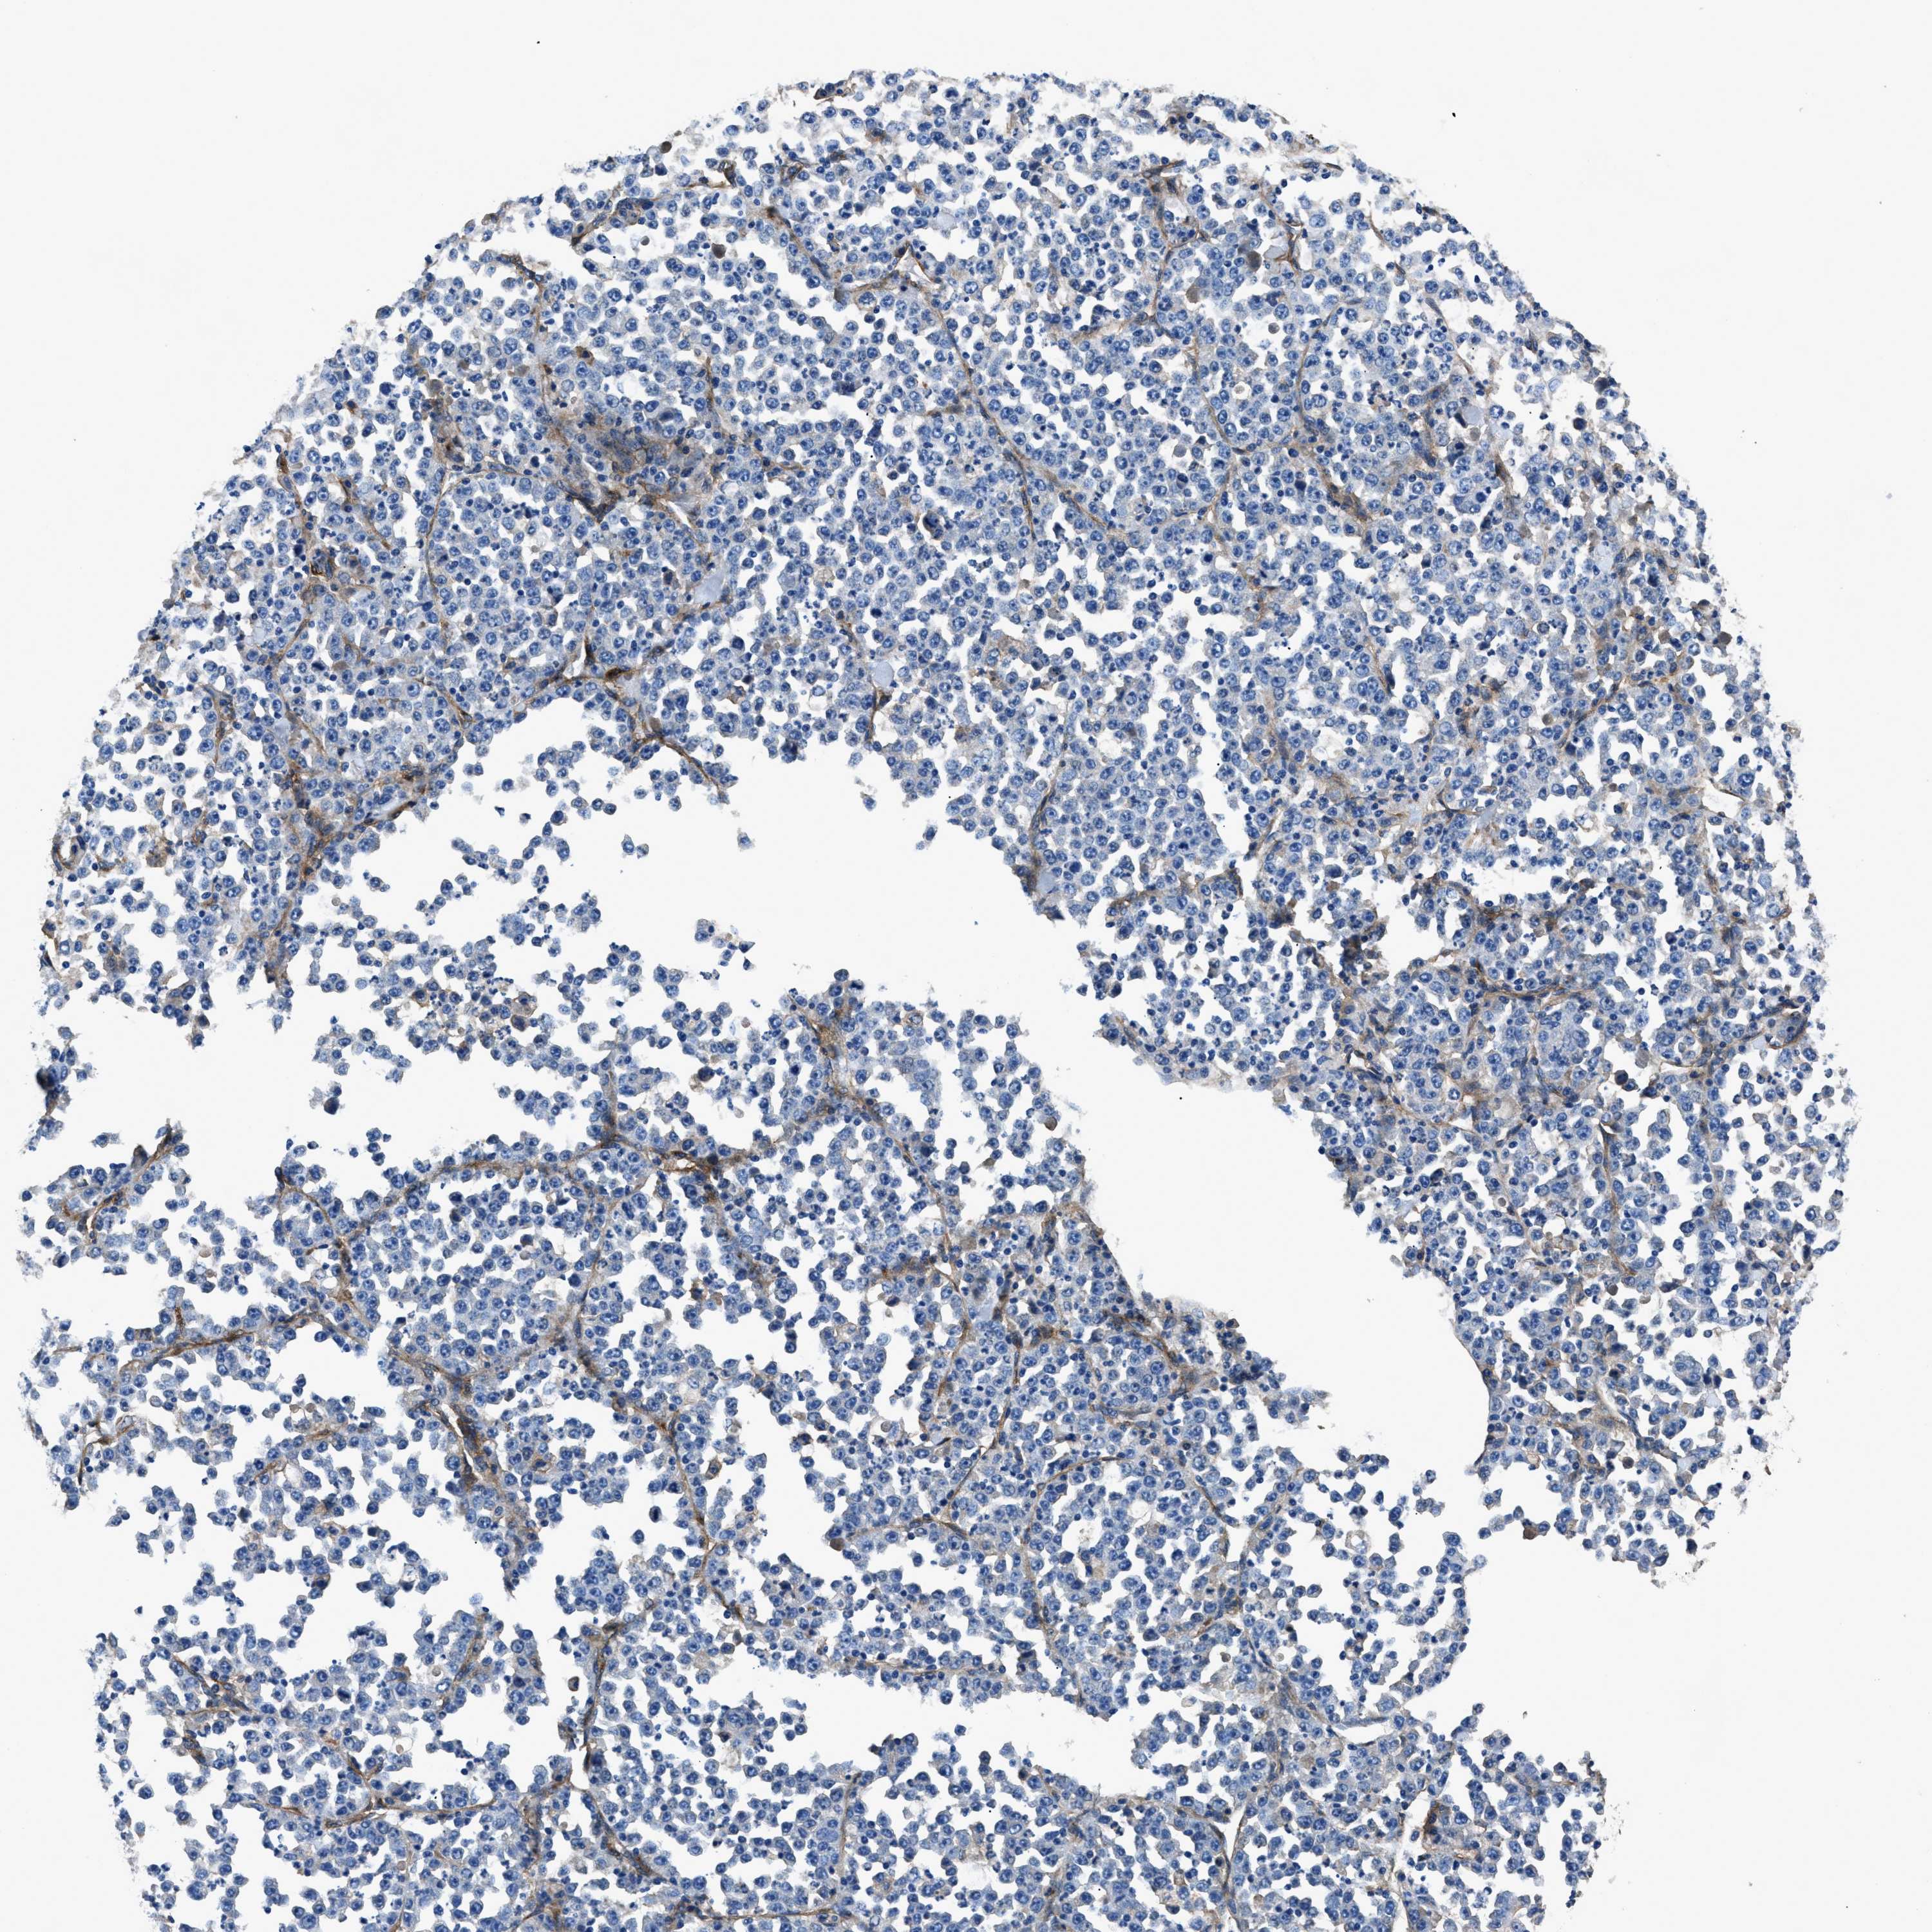

STOMACH CANCER - Protein expressioni

A mouse-over function shows sample information and annotation data. Click on an image to view it in a full screen mode. Samples can be filtered based on level of antibody staining by selecting one or several of the following categories: high, medium, low and not detected. The assay and annotation is described here.

Antibody stainingi

Antibody staining in the annotated cell types in the current human tissue is reported as not detected, low, medium, or high, based on conventional immunohistochemistry profiling in selected tissues. This score is based on the combination of the staining intensity and fraction of stained cells.

Each image is clickable and will lead to virtual microscopy that enables deeper exploration of all samples and also displays staining intensity scores, fraction scores and subcellular localization as well as patient and tissue information for each sample.

Antibody HPA009285

Antibody HPA017139

Antibody CAB017826

Staining

High

Medium

Low

Not detected

Intensity

Strong

Moderate

Weak

Negative

Quantity

>75%

75%-25%

<25%

None

Location

Nuclear

Cytoplasmic/membranous

Cytoplasmic/membranous,nuclear

Adenocarcinoma, NOS

Adenocarcinoma, High grade